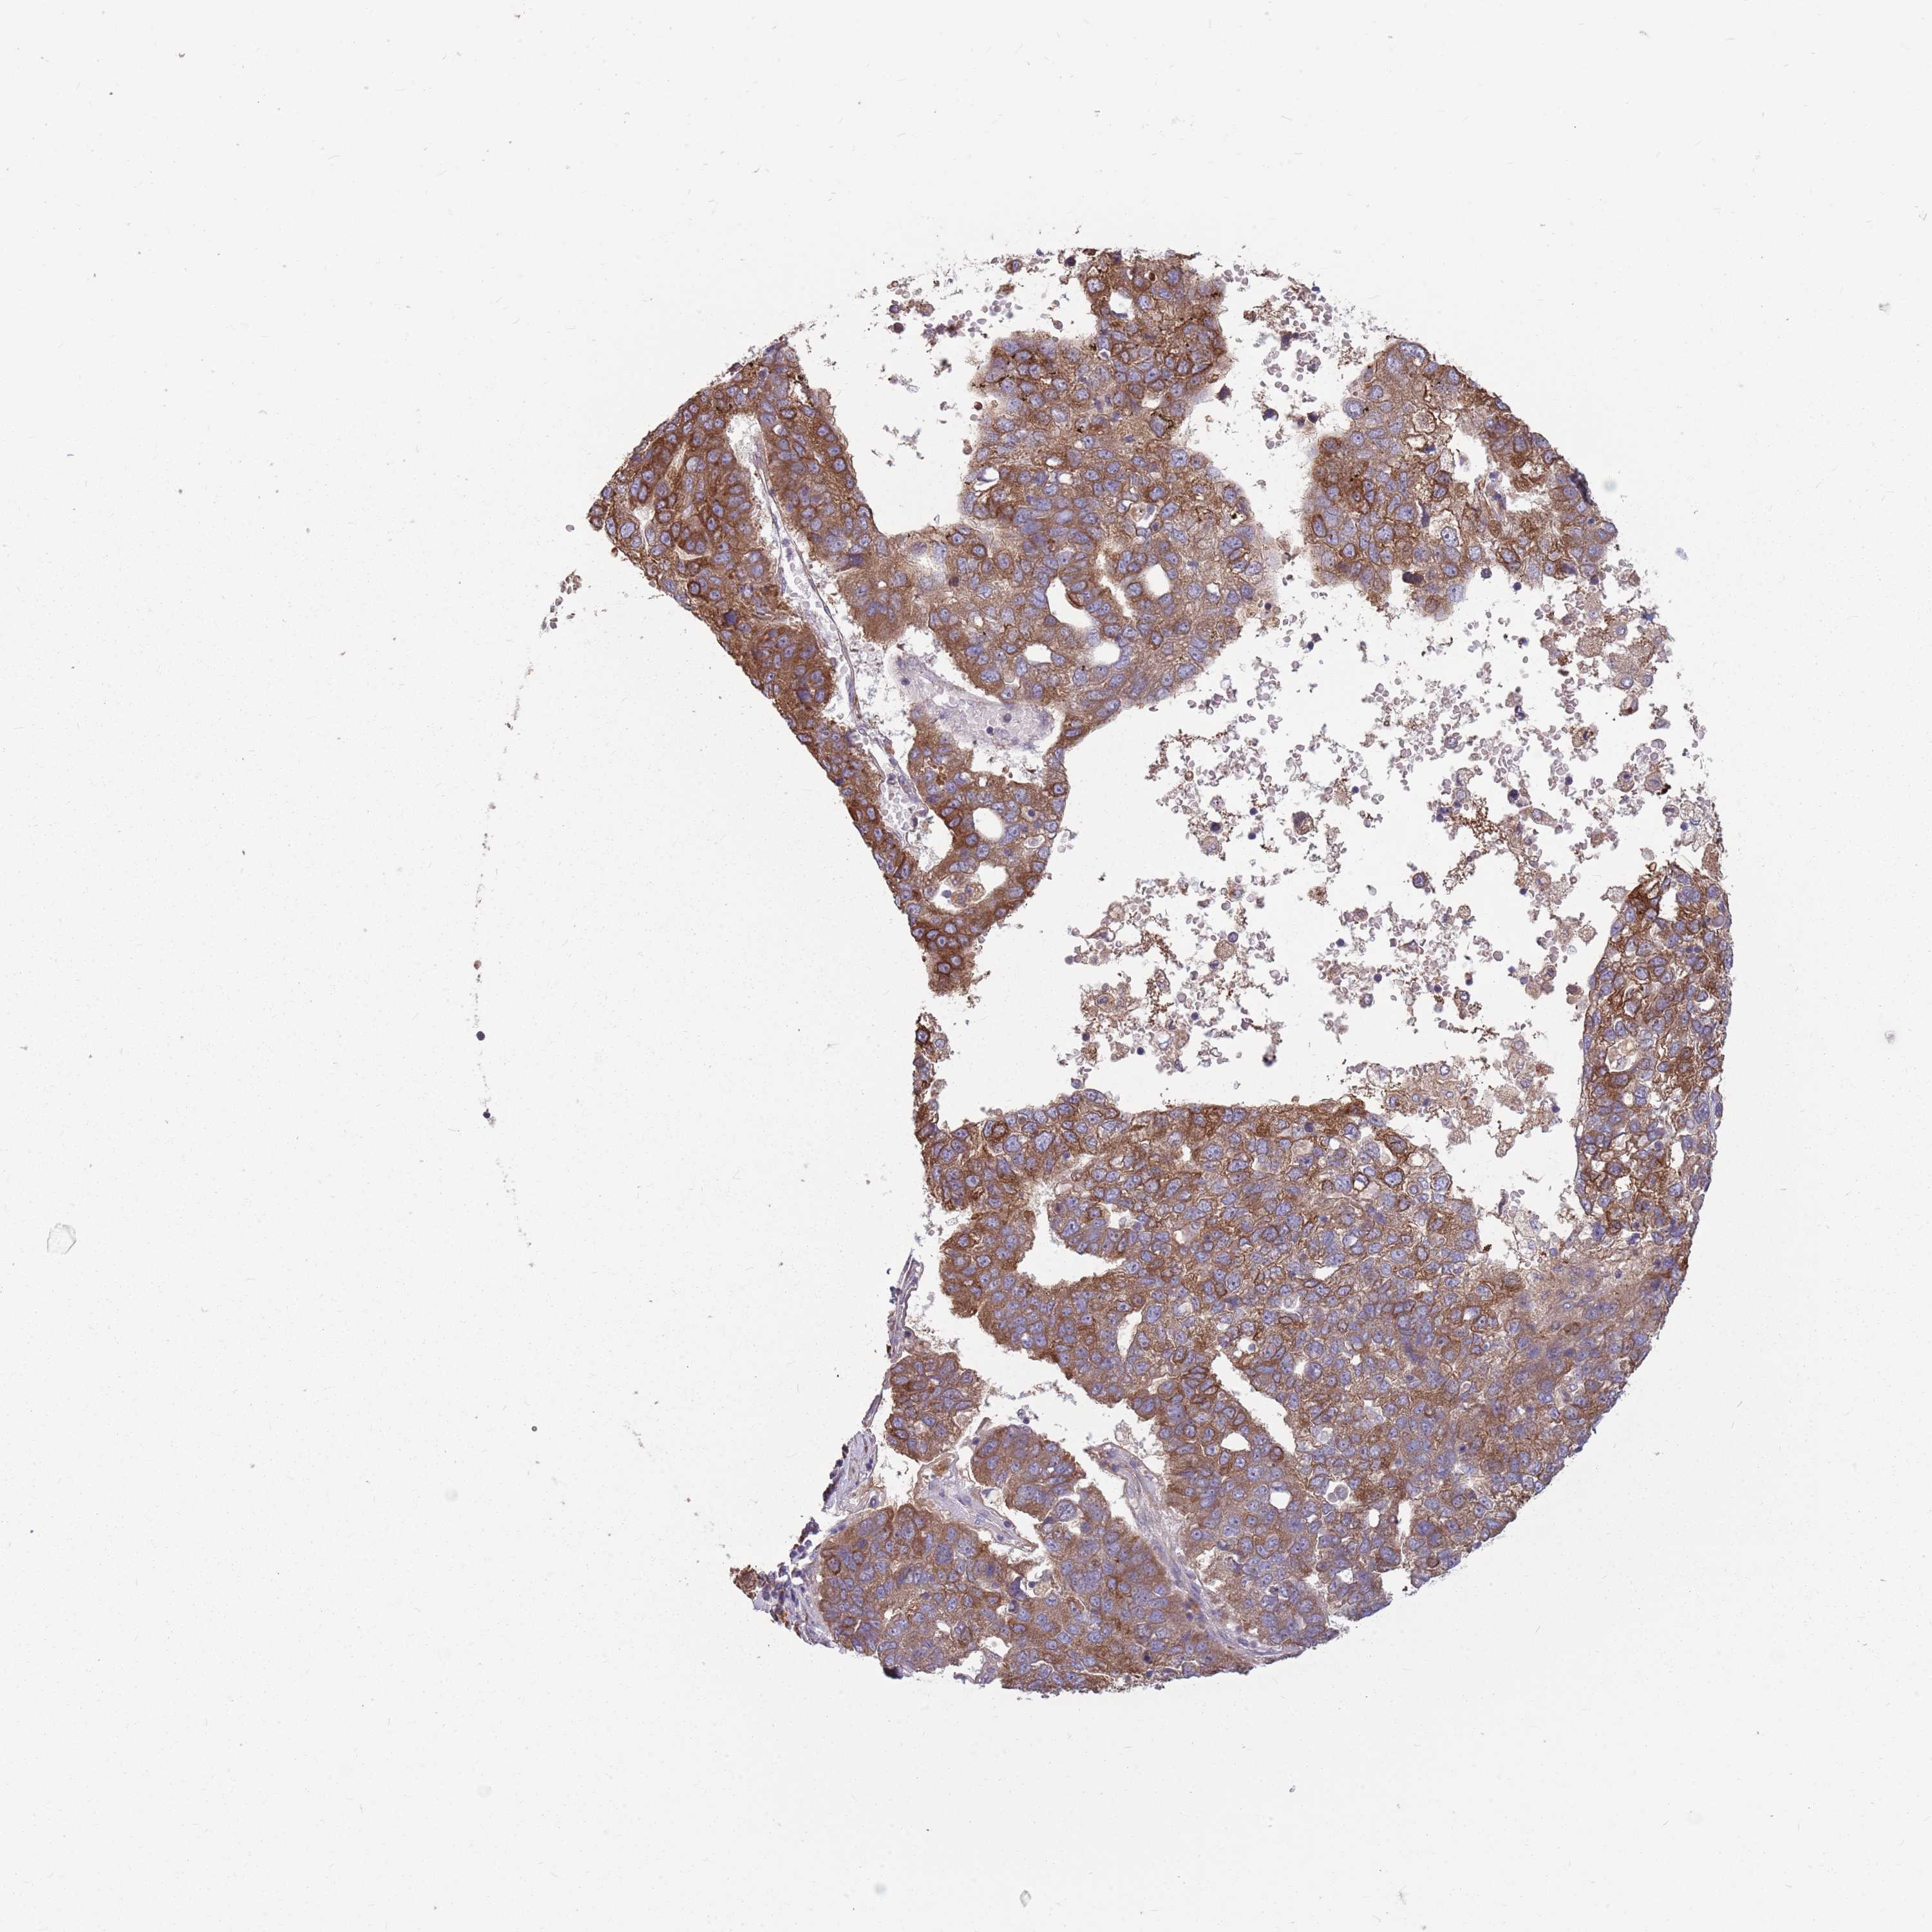

PANCREATIC CANCER - Protein expressioni

A mouse-over function shows sample information and annotation data. Click on an image to view it in a full screen mode. Samples can be filtered based on level of antibody staining by selecting one or several of the following categories: high, medium, low and not detected. The assay and annotation is described here.

Antibody stainingi

Antibody staining in the annotated cell types in the current human tissue is reported as not detected, low, medium, or high, based on conventional immunohistochemistry profiling in selected tissues. This score is based on the combination of the staining intensity and fraction of stained cells.

Each image is clickable and will lead to virtual microscopy that enables deeper exploration of all samples and also displays staining intensity scores, fraction scores and subcellular localization as well as patient and tissue information for each sample.

Antibody HPA048632

Staining

High

Medium

Low

Not detected

Intensity

Strong

Moderate

Weak

Negative

Quantity

>75%

75%-25%

<25%

None

Location

Nuclear

Cytoplasmic/membranous

Cytoplasmic/membranous,nuclear

Adenocarcinoma, NOS